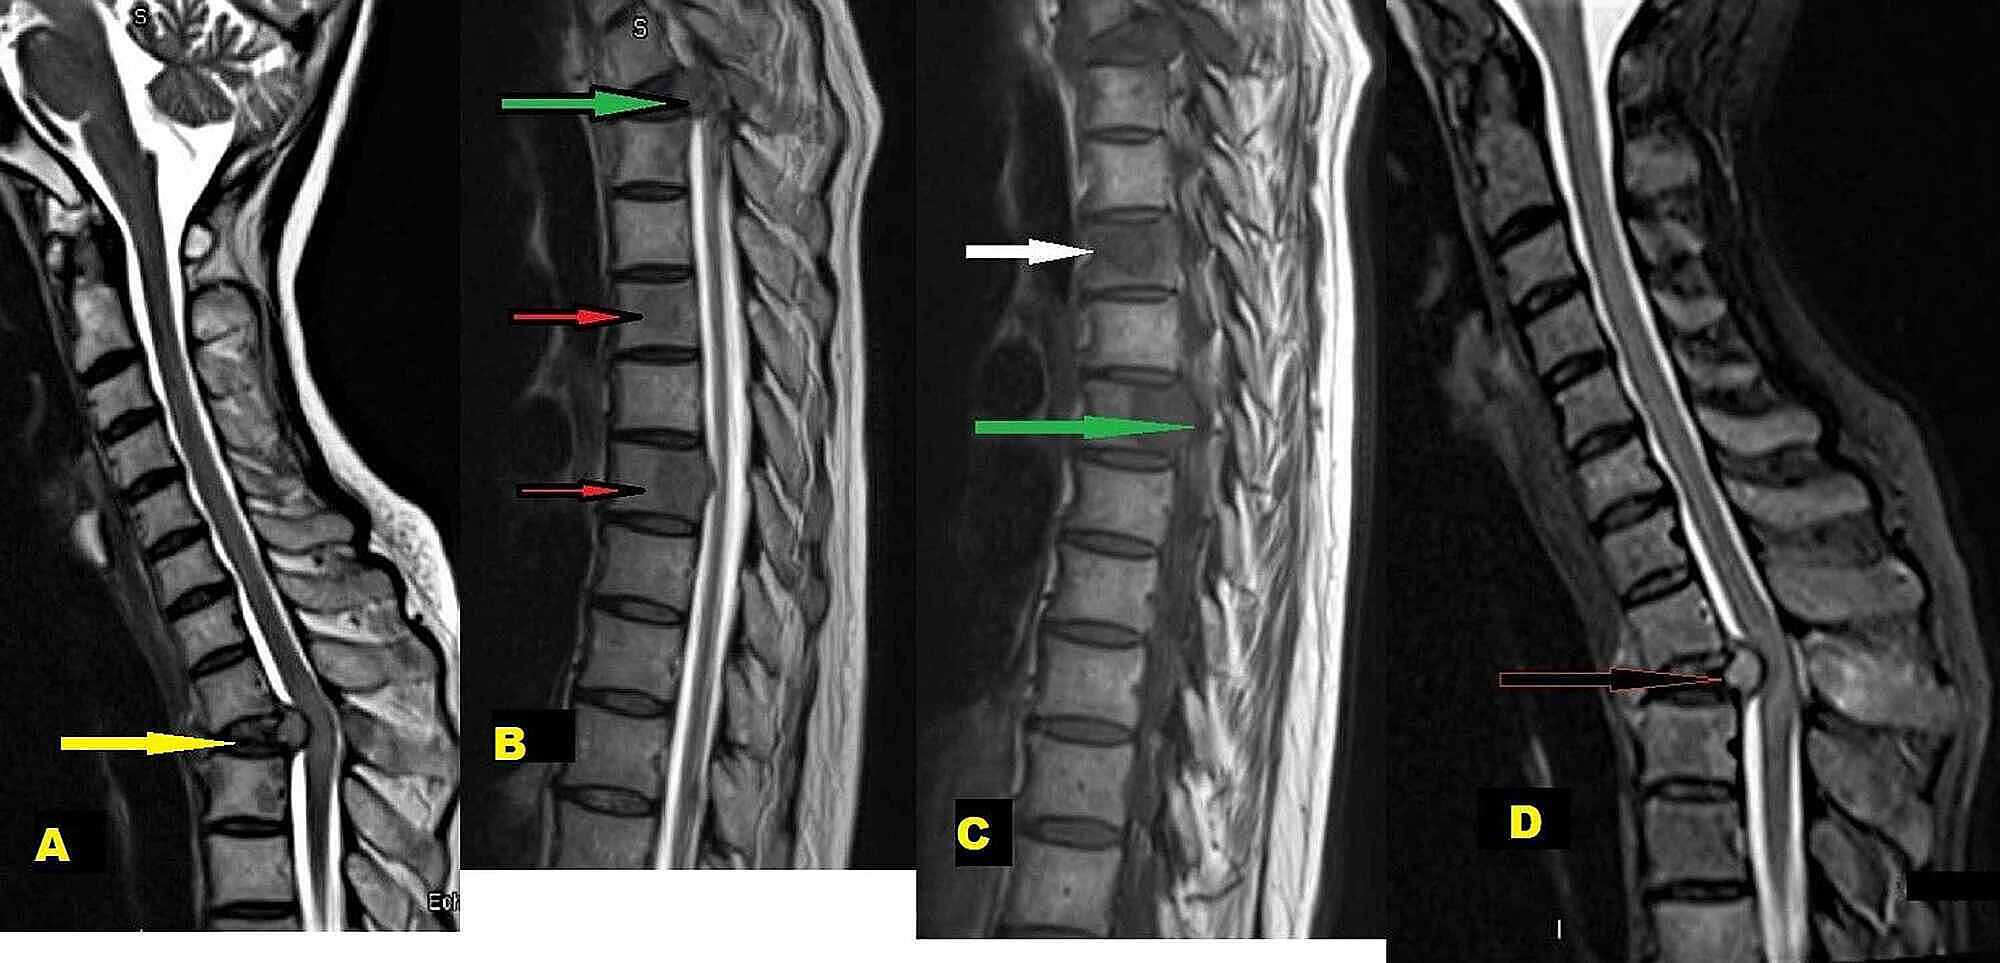

Differentiation Of Intraspinal Tuberculosis And Metastatic Cancer Usin Idr from www.dovepress.com She says she still does not know if she has had covid, but believes the pandemic. The occurrence of pulmonary tuberculosis (ptb) and lung cancer as comorbidities has been extensively discussed in many studies. Lung cancer is often divided into two types: Symptoms of tuberculosis and lung cancer are overlapping and it is difficult to differentiate without the histopathological report. 7 incidence the incidence of lung cancer in tuberculosis patients was about 2%. Since mycobacterium tuberculosis (mtb) is an intracellular organism, bacterial dna could integrate to bronchial epithelial cells inducing neoplastic transformation. Thus, multidisciplinary team from infectious department doctors and oncologists to share their opinion in the treatment this case. Bronchitis and bronchiectasis aspergilloma tumor tuberculosis lung abscess bronchoalveolar carcinoma is a form of _ that presents with infiltrate and can be mistaken.

Possible causes, signs and symptoms, standard treatment options and means of care and support. Tb is spread from person to person through the air. When people with lung tb cough, sneeze or spit, they propel the tb germs into the air. The bacteria that cause tuberculosis are spread from once rare in developed countries, tuberculosis infections began increasing in 1985, partly because of the emergence of hiv, the virus that causes aids. Interestingly so, tuberculosis has been known to mimic lung cancer due to its presentation in the form of pulmonary infiltrates and mediastinal lymphadenopathy however, in the reported cases where pulmonary tuberculosis was mistaken for pulmonary malignancy, a number of different, costly. Difference between lung cancer and tuberculosis. Tuberculosis (tb) and lung cancer are important global health threats, each accounting for 1.6 million deaths yearly. Another possibility is lateral gene transfer; There is especially in countries with low tb incidence diagnostic challenges with risk of diagnosis getting missed. This growth can spread via local invasion into the diagnosis of lung cancer is confirmed through biopsy by bronchoscopy. Helen has now had treatment for her lung cancer and is recovering well. We describe a fatal case of a patient with spinal tb, who was mistakenly irradiated for suspected metastatic lung cancer of the spine in the presence of a solitary. Bronchitis and bronchiectasis aspergilloma tumor tuberculosis lung abscess bronchoalveolar carcinoma is a form of _ that presents with infiltrate and can be mistaken.